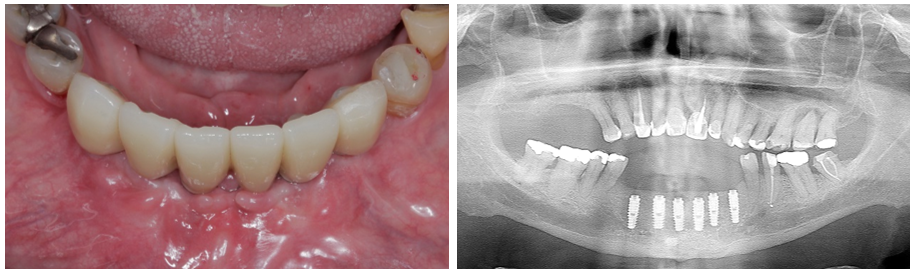

O planejamento reverso em Implantodontia assume importante papel no posicionamento 3D dos implantes. Nesse sentido, relatamos esse caso de ausência dos dentes anteriores inferiores (31/32/33/41/42/43) de um paciente usuário de prótese parcial removível que tinha o desenho de usar uma prótese fixa sobre implantes, como ilustrado nas imagens abaixo.